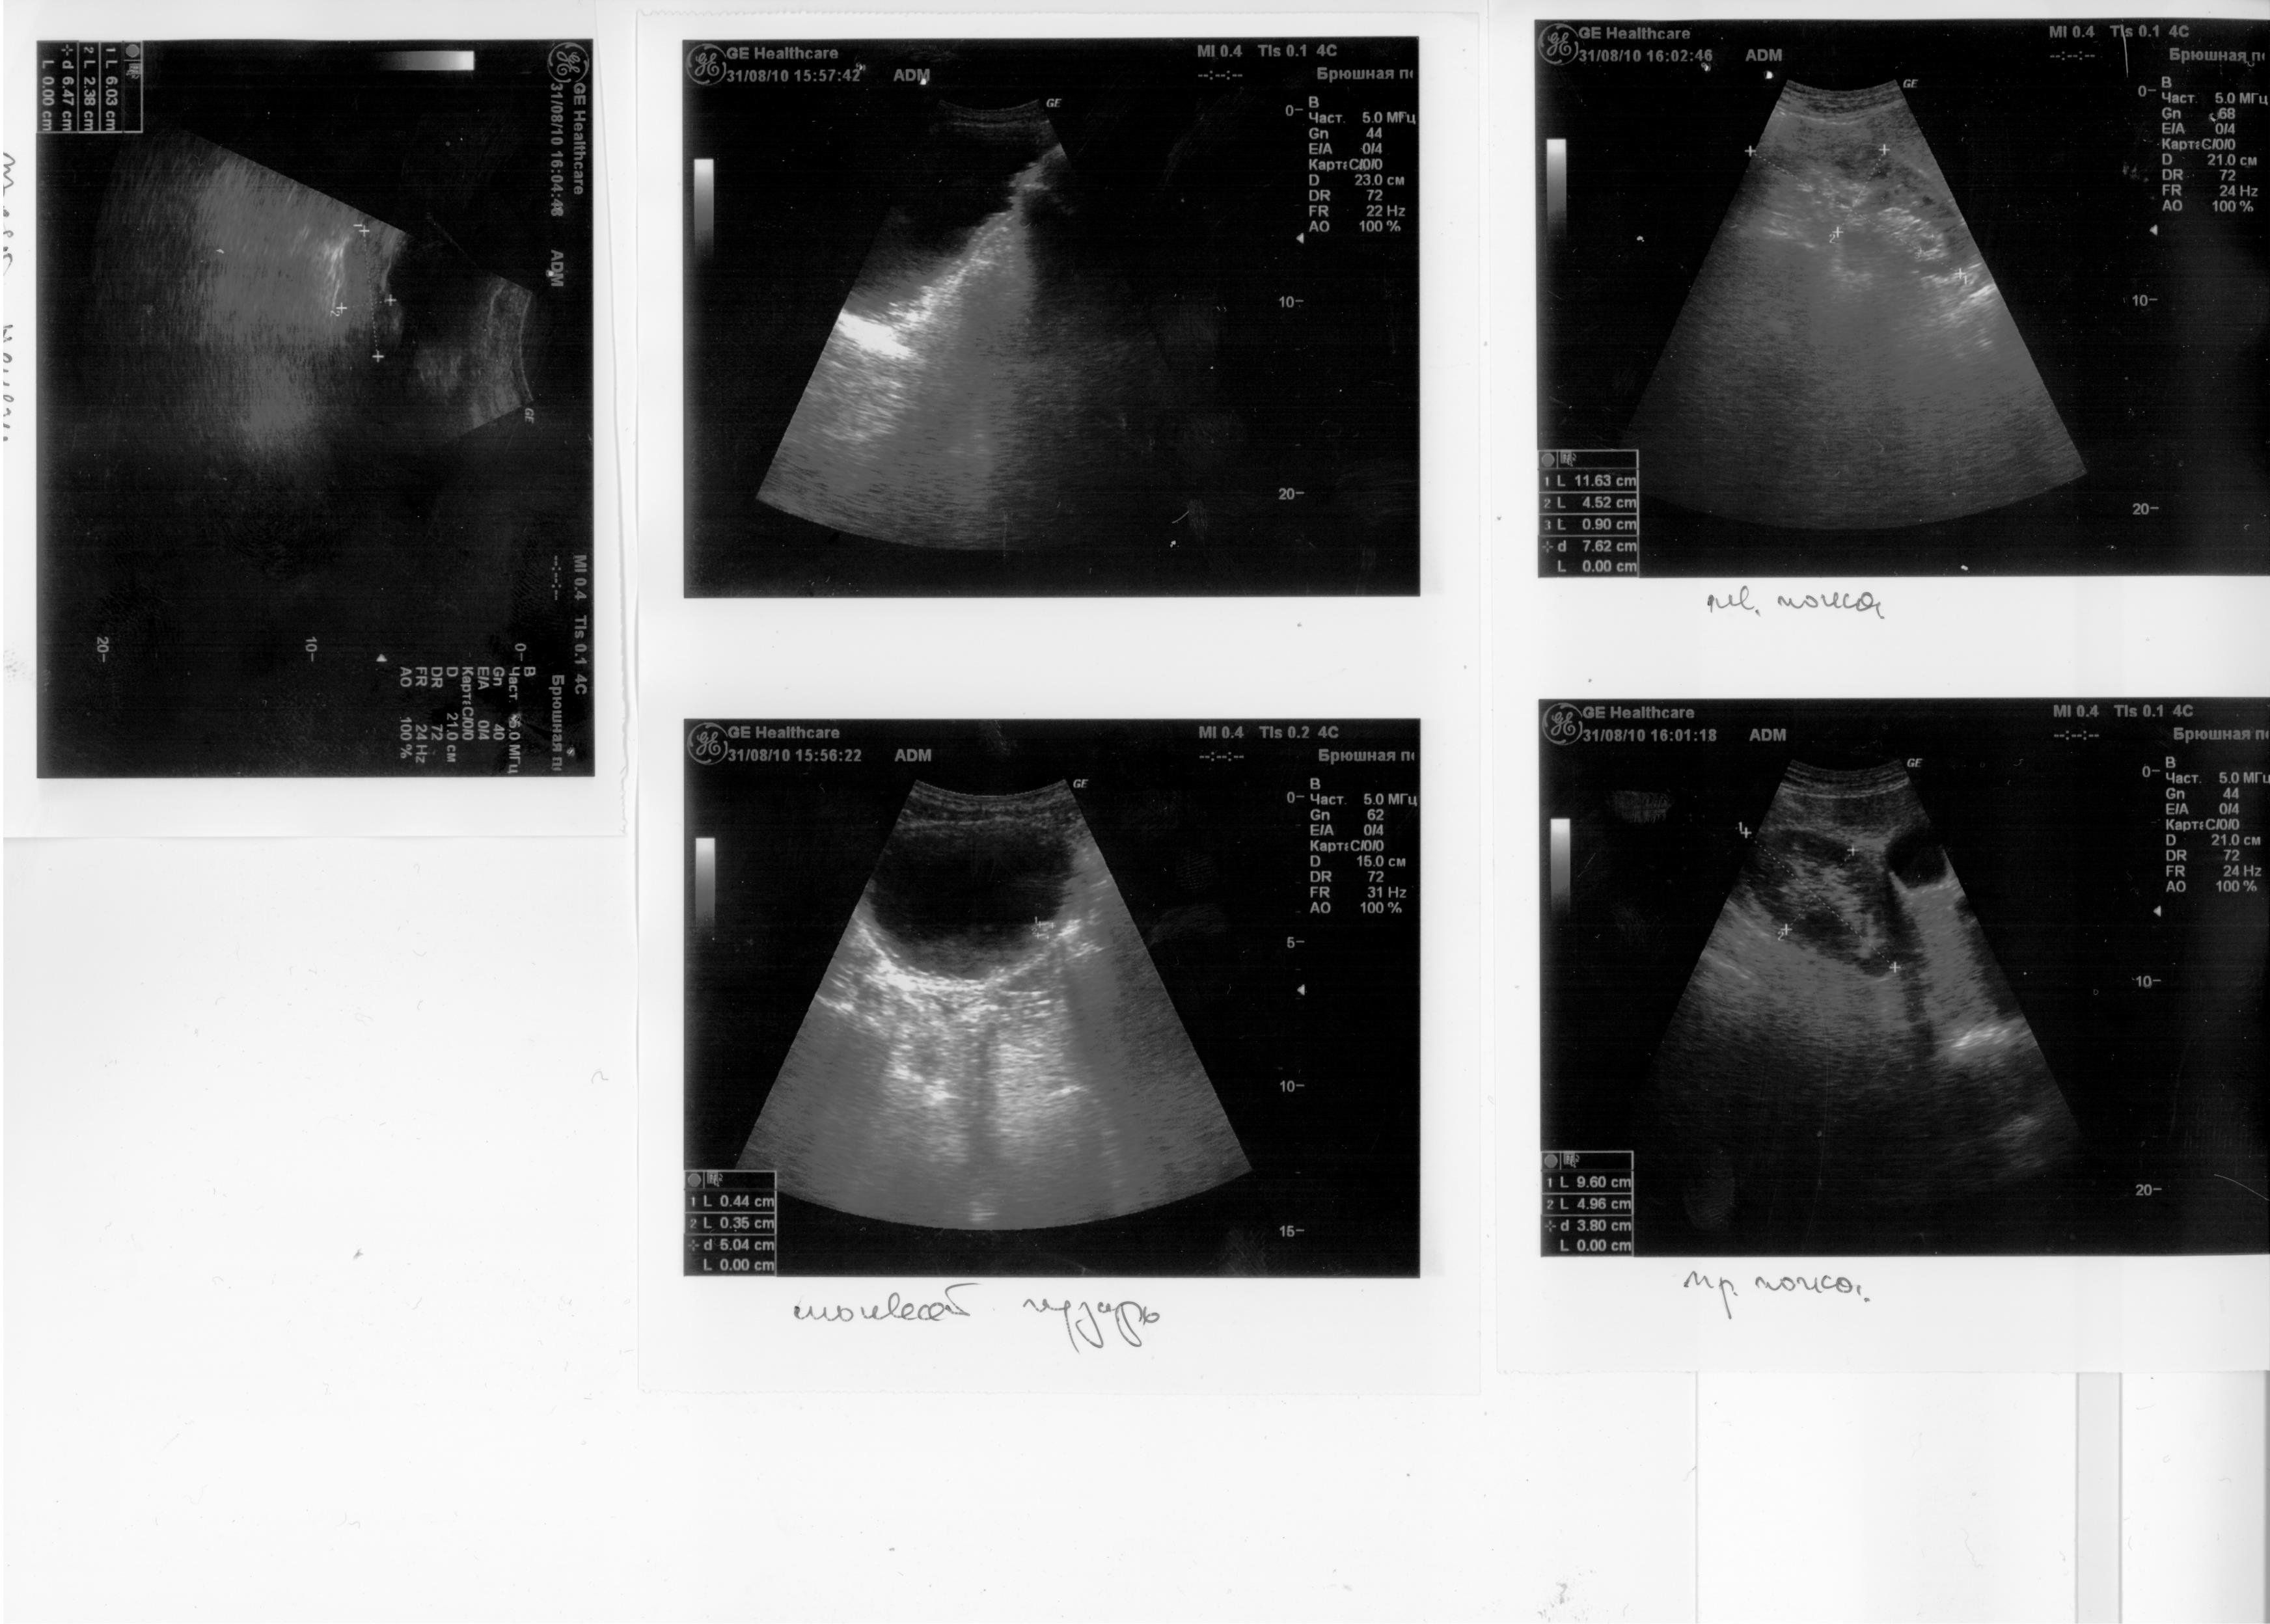

Здравствуйте. Травма С5 в 2003 г. Разница между обследованием 2, 2.1, 2.2 и 1, 1.1, 1.2 одна неделя. Остаточная моча 500-600мм. Уролог сказал, что надо ставить эпицистому, лечащий врач нейрохирург посоветовал не спешить, поставить катетер фолея на дней 10 опорожняя мочевой через каждые 5-6часов. У меня хр. цистит, хр. пиелонефрит. Посоветуйте пожалуйста что делать в данной ситуации? С уважением Руслан.